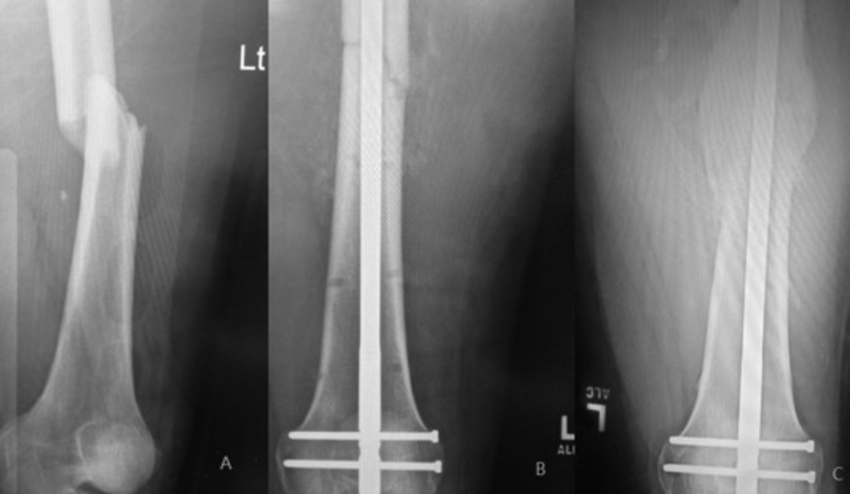

Intramedullary Nailing involves inserting a metal rod, or nail, into the central cavity of a long bone (the medullary canal). The nail is designed to keep fractured bone segments aligned and stable during healing. Once placed within the bone, the nail is secured with locking screws at each end to hold the fragments in place.

The Intramedullary Nailing Procedure

- Anaesthesia: Performed under general or regional anaesthesia to keep the patient comfortable.

- Incision and Access: A small incision is made near one end of the fractured bone to access the medullary canal.

- Insertion of the Nail: The surgeon carefully inserts the nail into the canal, positioning it to span the fracture site.

- Locking Screws Placement: Screws are placed through the bone and nail at each end to securely lock the nail in place, maintaining alignment and stability.

- Wound Closure: Incisions are closed, and a dressing is applied.

- Early Mobility: IM Nailing allows for early weight-bearing and movement, depending on the bone involved and the fracture’s stability.

- Healing Time: Bone healing varies based on the location and severity of the fracture but typically spans several months. The intramedullary nail provides stability throughout.

- Follow-Up: Regular follow-up visits ensure the bone is healing properly, with imaging to monitor progress.